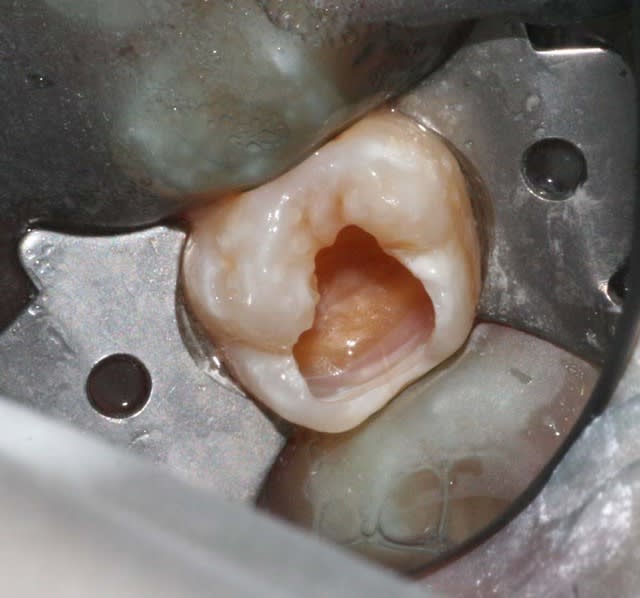

en parlant de compo, je sais que je suis pas au niveau des maitres du forum, mais ce matin je me suis un peu amusé.

c'est quoi ce truc métallique autour de la dent ? on dirait une sorte de pince avec une feuille plastique autour... ?